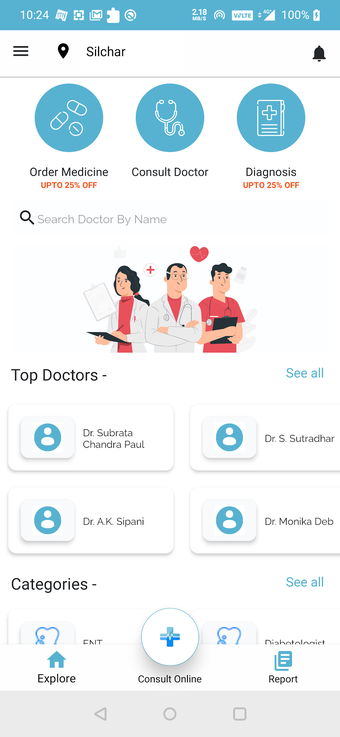

QuickOBook — Pacjent to aplikacja dotycząca stylu życia, która ma pomóc Ci znaleźć lekarza lub innego pracownika służby zdrowia w Twojej okolicy i umówić się na wizytę. Możesz użyć aplikacji do wyszukiwania lekarzy według ich nazwisk, specjalizacji lub przychodni.

Możesz wybierać spośród specjalistów dostępnych w Twojej okolicy.

Nazwisko lekarza, kwalifikacje, i dane uwierzytelniające są podane, dzięki czemu możesz zdecydować o jakości i wybrać tę, która najlepiej spełni Twoje potrzeby.

Quickobook czyni Cię prawdziwym pacjentem, łącząc się ty z lekarzem, którego potrzebujesz. Dzieje się tak, ponieważ możesz uzyskać dostęp do profilu lekarza wraz z innymi informacjami medycznymi i możesz porównać lekarzy lub specjalistów przed zaplanowaniem konsultacji.